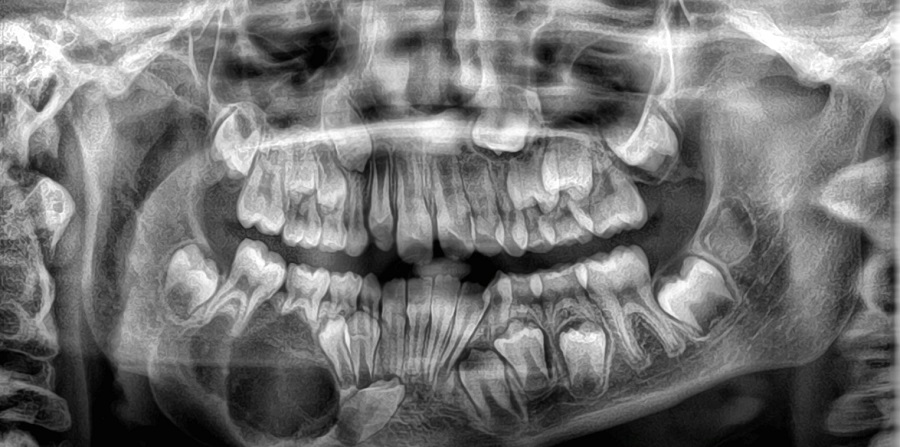

Paciente de 9 años que acude a consulta por bulto en zona mandibular de 2 meses de evolución, de consistencia dura, sin dolor ni inflamación asociada, ni infecciones previas. En ecografía clínica realizada en nuestro centro se objetiva lesión que produce protrusión de la cortical del hueso maxilar inferior, sin adherirse a tejidos blandos y con captación de Doppler de forma periférica. En la radiografía (Figura 1) solicitada posteriormente, se visualiza lesión lítica en rama derecha mandibular, expansiva, sin clara interrupción de la cortical que mide 3,6 cm, siendo sugestiva de benignidad. Con estos datos se deriva al paciente a Urgencias para valoración por Cirugía Maxilofacial, que amplía el estudio con analítica sanguínea, TAC (Figura 2) y ortopantomografía (Figura 3). Tras los resultados de las pruebas complementarias, entre los posibles diagnósticos diferenciales se encuentra el fibroma osificante de mandíbula. Se procede a su resección completa quirúrgica con buenos resultados y con biopsia que confirma el diagnóstico de fibroma osificante con focos sugestivos de quiste óseo aneurismático secundario. En el TAC de control se visualiza hueso inmaduro que ha ido ocupando la zona del defecto, sin evidenciarse recidiva.

Figura 1. Radiografía anteroposterior y lateral

Figura 3. Ortopantomografía